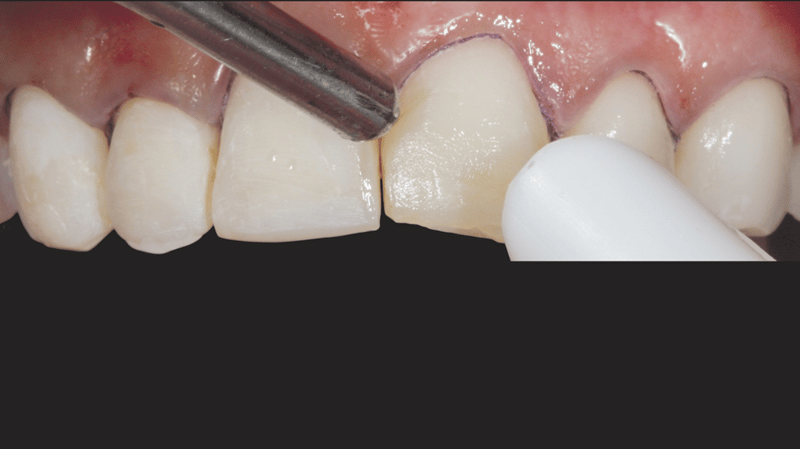

- Veneer Separation: A #12 blade and separating saw were used to carefully separate the veneers, ensuring precision.

- Gingival Sulcus Preparation: Ultrapak™ knitted cord Size #0 was packed into the gingival sulcus to prepare for etching.

- Cementation: The veneers were cemented using PermaShade™ LC luting resin in the Translucent shade (not available in Europe).